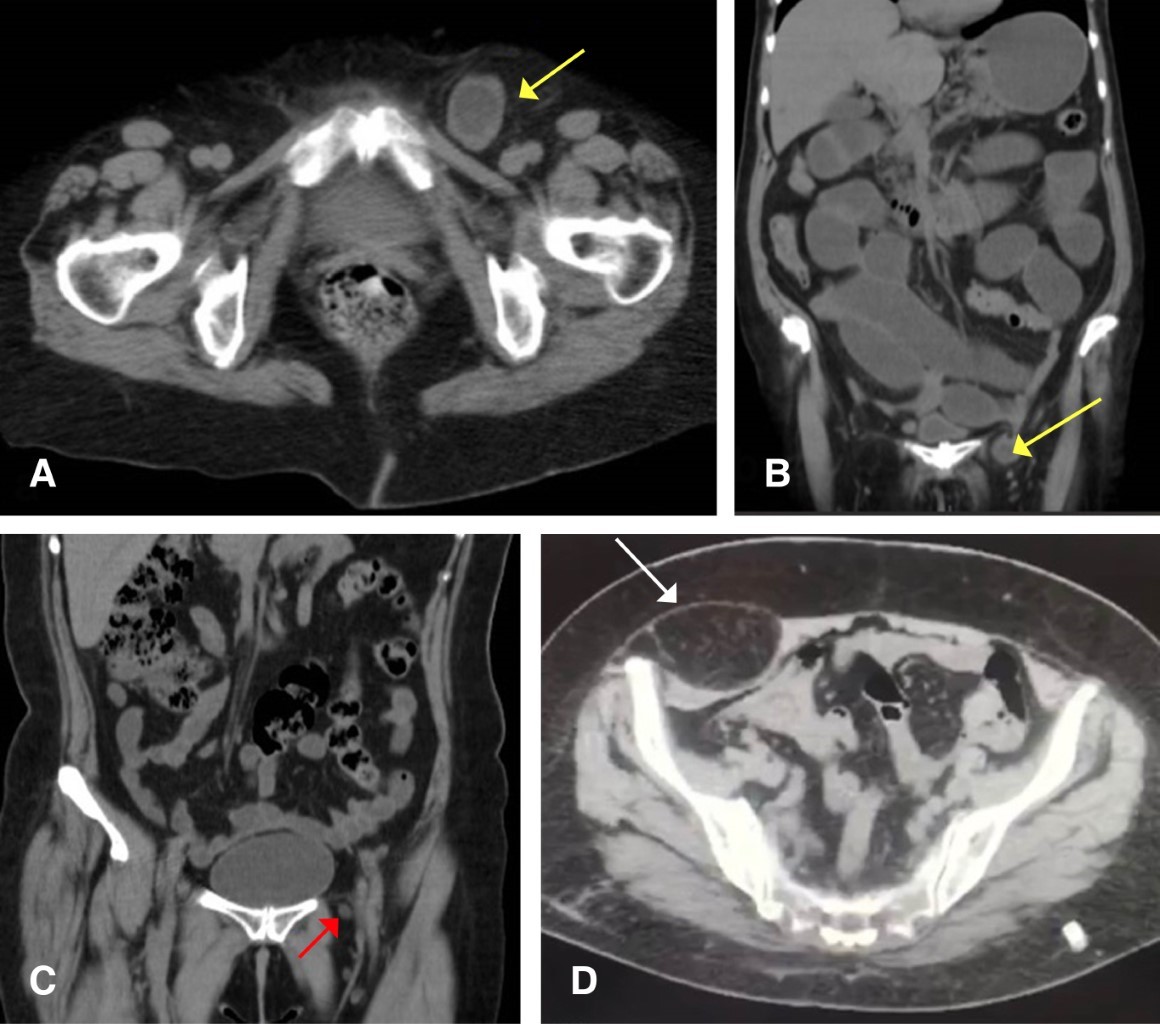

En todos los casos, se realizó tomografía abdominal simple previa al procedimiento quirúrgico (Figuras 1 y 2). En todos los pacientes se administró una dosis de antibiótico profiláctico (cefalosporina); en ambos pacientes sometidos a cirugía de urgencia, se continuó esquema antibiótico por siete días.

La tomografía se considera el estudio de elección en el diagnóstico de hernias poco frecuentes, como las descritas en nuestros casos.24 Debido a que presentan pocos síntomas y signos específicos, se requiere de la realización de este estudio de imagen para corroborar el diagnóstico, identificar las relaciones anatómicas, diferenciar la atrofia muscular y los abscesos de las hernias verdaderas, aportando una adecuada definición del defecto y contenido herniario, lo que permite optimizar el plan quirúrgico.10,24

Figura 1

Figura 2